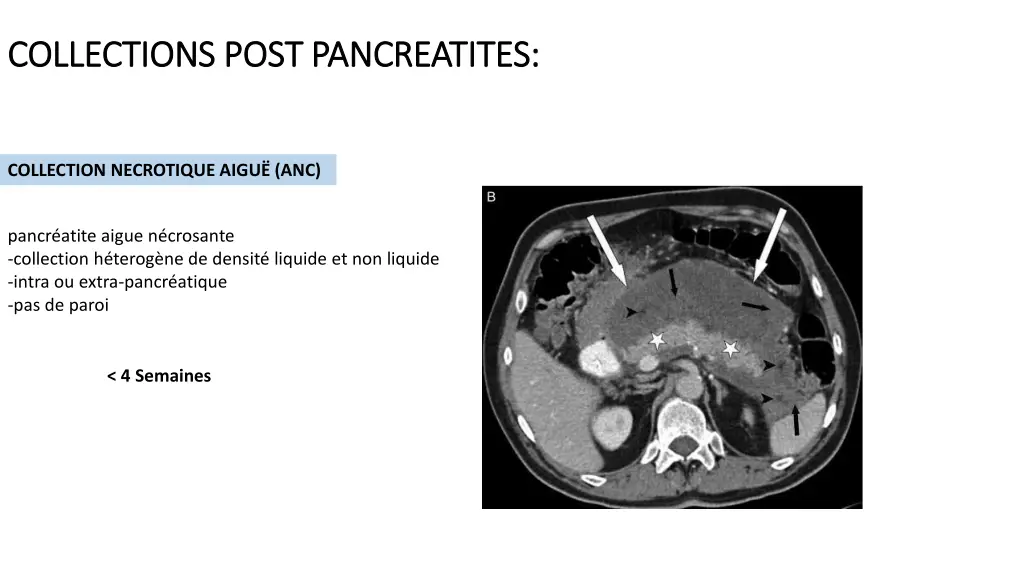

COLLECTIONS COLLECTIONS POST PANCREATITES POST PANCREATITES: : < 4 Semaines > 4 Semaines COLLECTION LIQUIDIENNE PERIPANCREATIQUE AIGU PSEUDOKYSTE PA Oed mateuse COLLECTION NECROTIQUE AIGU NECROSE CIRCONSCRITE (WON) PA N crosante

COLLECTIONS COLLECTIONS POST PANCREATITES POST PANCREATITES: : COLLECTION NECROTIQUE AIGU (ANC) pancr atite aigue n crosante -collection h terog ne de densit liquide et non liquide -intra ou extra-pancr atique -pas de paroi < 4 Semaines